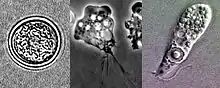

| مراحل گوناگون زندگی نگلیریا | |

این آمیب در طول چرخهٔ حیات خود، به سه صورت مختلف میتواند درآید:

- کیست (Cyst)

- آمیب تاژکدار (Flagellate)

- تروفوزوئیت (Trophozoite)

نوع کیستی آن تنها زمانی ایجاد میشود که شرایط محیطی برای ادامه زندگی این تکیاخته، دشوار باشد (همانند کمبود مواد مغذی) و در واقع این تکیاخته با تبدیل شدن به فرم کیستی، خود را از شرایط ناهموار و نامناسب محیط، حفظ میکند. در بدن انسان هرگز نوع کیستی یا تاژکدار دیده نمیشوند و تنها نوع تروفوزوئیت آن است که میتواند منجر به بیماری گردد. نگلیریا از باکتریهای دیگر تغذیه میکند.[2]